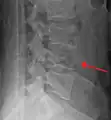

A burst fracture of L4 as seen on plane X ray -

A burst fracture of L4 as seen one plane X ray -